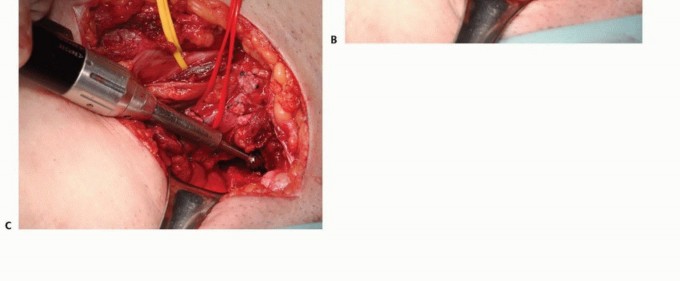

يُعد الأستاذ الدكتور محمد هطيف، بخبرته الواسعة التي تتجاوز 20 عامًا ودقته المتناهية في جراحة العظام، الرائد الأول في علاج نقائل الحوض في صنعاء واليمن. بصفته أستاذًا في جامعة صنعاء، يتبنى الدكتور هطيف منهجًا شاملاً يركز على استعادة وظيفة المريض وتخفيف الألم وتحسين نوعية حياته، باستخدام أحدث التقنيات الجراحية وأفضل الممارسات العالمية. يُدرك الدكتور هطيف أن الأورام اللحمية الأولية والأورام النقائلية غالبًا ما تتمدد بشكل كبير إلى الأنسجة الرخوة المحيطة، ولكن نظرًا لحساسيتها المتأصلة للعلاج الإشعاعي، فإن الإدارة الجراحية للآفات النقائلية لا تتطلب بالضرورة استئصالًا كاملاً للعضلات المغطية، حيث يمكن معالجة البقايا المجهرية بالإشعاع المساعد بعد الجراحة. يتطلب التشريح المعقد للحوض تخطيطًا تفصيليًا قبل الجراحة، وتحديدًا لتقنية التعرض وإعادة البناء، وتنفيذًا دقيقًا ومتقنًا للإجراء الجراحي لضمان أفضل النتائج للمريض.